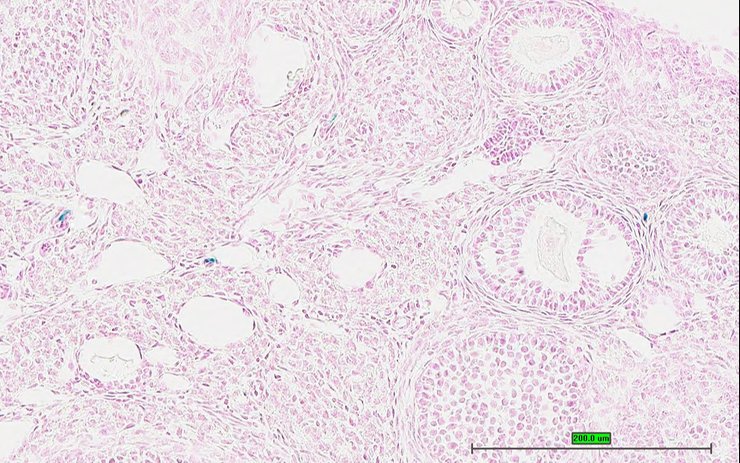

Specimen UC Davis_1879028: postnatal adult; Pmchtm1.1(KOMP)Vlcg/Pmch+ (more )

Structure Level Pattern Image Note

TS28: stomach Present UC Davis_1879028